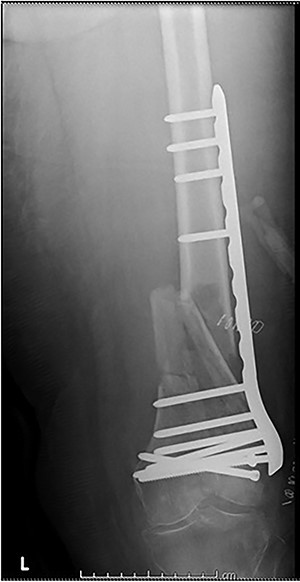

Case 4 (Figs 8–10): once again, screw placement too close to the fracture site has resulted in internal plate stresses exceeding its load-bearing capacity.

Inter-fragmentary screws have been utilized here. This lady may have benefited from placing an anterior bridging plate at the time of her original procedure if it was not possible to avoid this screw configuration.